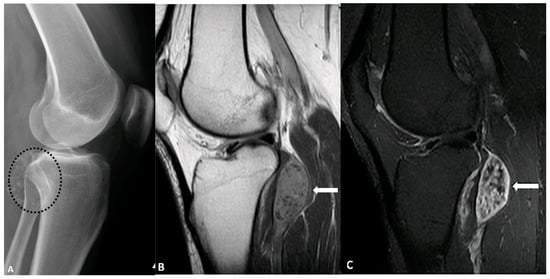

5.4. Synovial Chondromatosis

- Murphey, M.D.; Vidal, J.A.; Fanburg-Smith, J.C.; Gajewski, D.A. Imaging of synovial chondromatosis with radiologic-pathologic correlation. Radiographics 2007, 27, 1465–1488. [Google Scholar]

- Walker, E.A.; Murphey, M.D.; Fetsch, J.F. Imaging characteristics of tenosynovial and bursal chondromatosis. Skelet. Radiol. 2011, 40, 317–325. [Google Scholar]

- Norman, A.; Steiner, G. Bone erosion in synovial chondromatosis. Radiology 1986, 161, 749–752. [Google Scholar] [CrossRef] [PubMed]

- Kim, S.H.; Hong, S.J.; Park, J.S.; Cho, J.M.; Kim, E.Y.; Ahn, J.M.; Park, Y.S. Idiopathic synovial osteochondromatosis of the hip: Radiographic and MR appearances in 15 patients. Korean J. Radiol. 2002, 3, 254–259. [Google Scholar] [CrossRef] [PubMed]